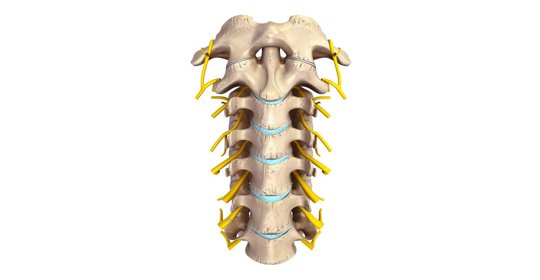

神經阻斷術後遺症的症狀表現、前兆、治療及預防

橋腦中風後遺症的症狀、前兆、治療與預防